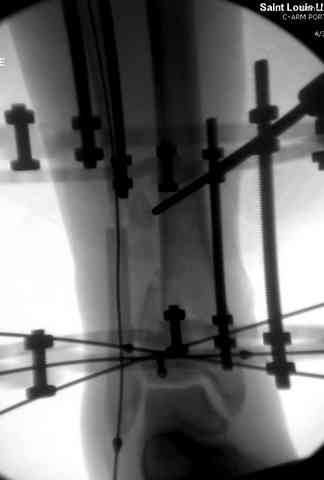

В первые часы после поступления больным экстренно накладывается простой фиксатор из двух поперечно проведенных стержней или сооружается "Delta

Frame" в зависимости от места локализации, и проводится дистракция.

Преимуществ у временного фиксатора много, во первых больной независим, если по другим показаниям нет необходимости находиться в стационаре, то больной может быть выписан домой с возможностью в амбулаторных условиях оценивать состояния мягких ткани на готовность к операции.

Наружным фиксатором обеспечивается длина конечности, предупреждается вторичное сокращение мягких ткани, что является немаловажным фактором для заживления послеоперационных ран. Без фиксатора сокращенные мягкие ткани легко травмируется во время манипуляций, трудно будет провести репозицию, ухудшается местное кровообращение и сохраняется посттравматический отек.

Здесь выставлена пара случаев перелома пилона, оба

случая леченные этапным наружным фиксатором.